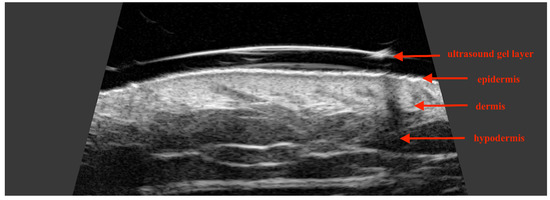

1.2. Normal Facial Skin Ultrasound: Characteristics and Potential Applications

- Barcaui Ede, O.; Carvalho, A.C.; Piñeiro-Maceira, J.; Barcaui, C.B.; Moraes, H. Study of the skin anatomy with high-frequency (22 MHz) ultrasonography and histological correlation. Radiol. Bras. 2015, 48, 324–329. [Google Scholar]

- Mlosek, R.K.; Malinowska, S. Ultrasound image of the skin, apparatus and imaging basics. J. Ultrason. 2013, 13, 212–221. [Google Scholar] [CrossRef]